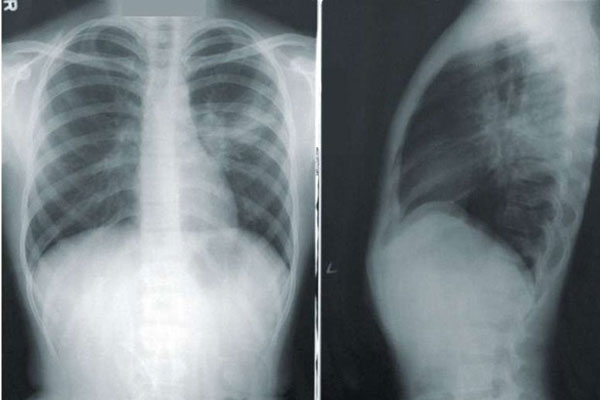

Ngón tay dùi trống hay chứng ngón tay hình chùy là một sự biến dạng của các móng tay hoặc móng chân liên quan nhiều loại bệnh tật, chủ yếu là các bệnh về tim và phổi. Móng tay dùi trống vô căn có thể xảy ra, nhưng là một tình trạng hiếm. Ngón tay dùi trống xảy ra khi mô mềm ở đầu ngón tay sưng lên và làm cho móng tay thay đổi hình dạng. Các cơ chế chính xác vẫn chưa rõ ràng, nhưng các chuyên gia tin rằng nó có thể do sự sản xuất quá mức của yếu tố tăng trưởng nội mô mạch máu (VEGF), một loại protein hướng dẫn mạch máu phát triển. Điều này dẫn đến tăng lưu lượng máu đến các khu vực như ngón tay, cũng như sự tích tụ chất lỏng khắp cơ thể gọi là phù và viêm.